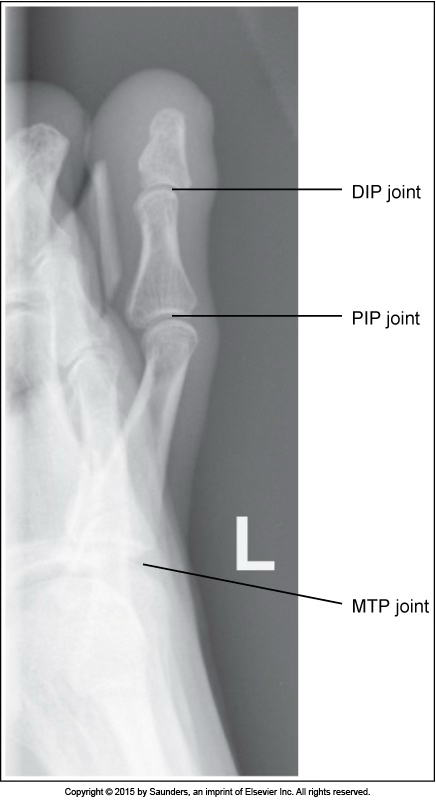

lateral toe

accurate positioning